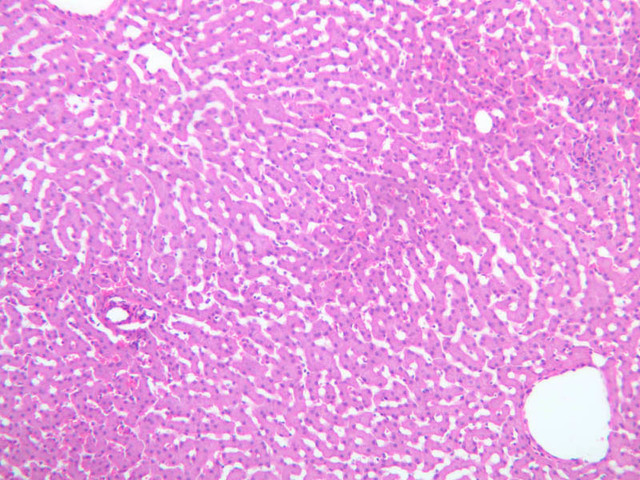

Examine the H&E-stained sections of liver (slides B-29 [10x, 20x, 40x-labeled] [2.5x-labeled, 10x, 20x, 40x] [10x-labeled, 20x, 40x-labeled] and B-30 [2.5x, 10x-labeled, 20x]). At low power, identify the connective tissue capsule (Glisson’s capsule), central veins and portal triads (portal canals). Note that the cells of the liver parenchyma (hepatocytes) appear as cords--more accurately, plates--of cells that radiate out from the central veins and partially enclose blood spaces known as hepatic sinusoids. Note that the plates of hepatocytes appear to branch and fuse and that, as a rule, they are only one or two cells thick. Do you see any binucleate hepatocytes?

Using the 10X (B-29, B-30)and 40X (B-29) objectives, examine several portal triads, noting the variable number of profiles of hepatic artery, portal vein and bile duct that comprise the portal triad. Near the boundary between adjacent lobules, try to find some of the small elements of the bile duct system known as canals of Hering.

Using the high dry objective, study the lining of the central vein and hepatic sinusoids (B-29). In some places the hepatocytes are exposed directly to the sinusoidal lumen, but, as a rule, there is a basal lamina which supports a discontinuous mosaic of endothelial cells and specialized phagocytic cells known as Kupffer cells. Find examples of Kupffer cells and endothelial cell nuclei. Note that in some places you may see a narrow space (the space of Disse) between hepatocytes and the basement membrane underlying endothelial and Kupffer cells. Using the oil immersion (100X) objective, look very carefully along the boundaries between adjacent hepatocytes to see if you can find a bile canaliculus--the most delicate portion of the bile duct system--the walls of which are formed by the plasma membranes of adjacent hepatocytes.

(1) Identify the portal triads that define the boundaries of a “classic” liver lobule (B-29). Since it surrounds a central vein, the classic lobule may be thought of as emphasizing the endocrine functions of the liver.

(2) Move the slide so that a portal triad is at the center of the microscopic field, then identify the three central veins that define the boundaries of the portal lobule that surrounds the reference portal triad. Since an interlobular bile duct is at the center of a portal lobule, the portal lobular interpretation emphasizes the exocrine functions of the liver (B-31).

(3) A liver acinus is roughly elliptical in section. Its shorter axis (equator) is defined by the terminal branches of the hepatic artery and portal vein, which course along the boundary between adjacent classic lobules; its longer axis is defined by the two central veins nearest the equator (B-29). Although it is more difficult to visualize a liver acinus than a classic or portal lobule, the concept of acinar organization is very useful because certain features of liver metabolism best fit the acinar model.